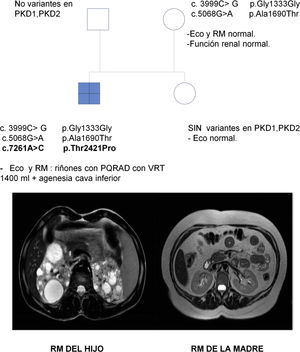

Se trata de una mujer de 47 años remitida a consulta de nefrología desde atención primaria para realizar un seguimiento por poliquistosis renal autosómica dominante (PQRAD). Su hijo, de 17 años, ha sido incidentalmente diagnosticado de PQRAD, según los criterios de Pei et al.1 en el contexto de dolor abdominal. Se llevó a cabo un estudio genético en el hijo para confirmar el diagnóstico, debido a la ausencia de antecedentes familiares de la enfermedad y a la existencia de estudios ecográficos normales en todos los familiares de primer grado. Se identificaron tres variantes en heterocigosis en el gen PKD1, no descritas hasta el momento, y que se clasifican de significado incierto. Sin embargo, los análisis in silico las califican como patogénicas (tabla 1). La paciente está asintomática, PA 110/60 mmHg, creatinina sérica 0,68 mg/dL, sin alteraciones urinarias y la ecografía renal es completamente normal. Se realiza un estudio genético, que identifica en heterocigosis las variantes c.3999C> G y c.5068G> A en el gen PKD1, previamente localizadas en su hijo. En esta situación, se repite una nueva ecografía renal, que vuelve a no presentar hallazgos patológicos, por lo que se realiza una resonancia abdominal en la que tampoco se encuentra ninguna anormalidad (fig. 1).

Se efectuaron estudios genéticos al padre y a la hermana del caso índice en el contexto de estudio de segregación y no se identificó variante alguna (fig. 1).

El hijo ha heredado las dos variantes en el gen PKD1 vía materna, y muestra otra (c.7261A> C), que se sospecha que podría ser de novo. Esta no está descrita y produce, a nivel proteico, un cambio de una treonina por una prolina en la posición 2421, el análisis in silico le asigna un carácter patogénico.